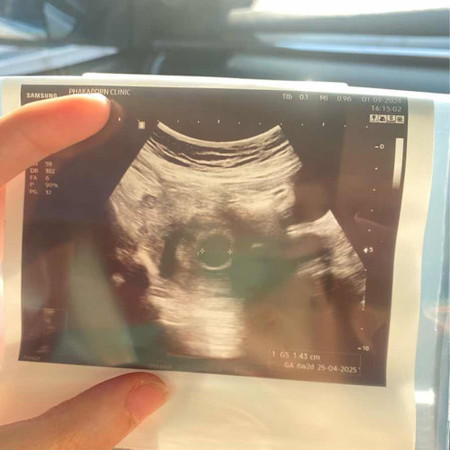

เพิ่งซาวด์วันนี้ ประจำเดือนล่าสุด 14/7/67 แม่ๆ เห็นน้องกี่วีคกันค่ะ กังวลว่าจะท้องลม หมอนัดตรวจ อีกที 2 อาทิตย์ค่ะ

เราอายุครรภ์เท่ากันเป๊ะเลยค่ะ ของเราซาวด์ตอนแรกก็ไม่เจอแต่พอหมอลองกดแรงๆก็เห็นตัวน้องค่ะ น้องอาจจะยังจิ๋วมากเลยยังไม่ชัดเหมือนของเราก็ได้ค่ะ ยังไงรอดูนัดครั้งต่อไปนะคะ

เราเมนมาล่าสุด 22/6/67 ในเแอปขึ้น8สัปดาห์5วัน แต่ไปฝากครรภ์ 26/8/67 ซาวได้7w5 เองค่ะ น้องยังตัวเล็กมาก ยังฟังเสียงหัวใจไม่ได้ เป็นก้อนจิ่วๆ

ของเค้าประจำเดือนล่าสุด 9/7 ซาวตอน7w6d เจอน้องแล้วนะคะ มีหัวใจเต้นแล้ว เห็นบางคนเจอน้องตอน10wกว่าเลยก็มี คุณแม่ไม่ต้องเครียดนะคะ 🥰

ของเราประจำเดือนล่าสุด 11/7 ตามแอพ 7 วีค 6 แล้ว ยังไม่กล้าไปซาว์ดค่ะ กลัวว่าต้องยังจิ๋วมากเดี่ยวไม่เห็น

เหมือนกันเลยค่ะ ทุกอย่างคงต้องรอเหมือนกันค่ะสู้ๆขอให้เจอน้องไปด้วยกันนะคะ เราปจด.มาล่าสุด 17/7

บ้านนี้ ประจำเดือนล่าสุด 8/7 หมอนัดซาวอีกทีวันที่9ไม่รู้จะเจอน้องมั้ยเหมือนกันค่ะ

ของเราไปตรวจตอน6วีค เจอแต่ถุงค่ะ อีก5วันไปซาวเจอตัวเล็กแล้วค่ะ 🥰🥰

9วีค3วันค่ะซาวผ่านหน้าท้องครั้งเเรกก้เจอเลยค่ะ👶🏻🫶🏻